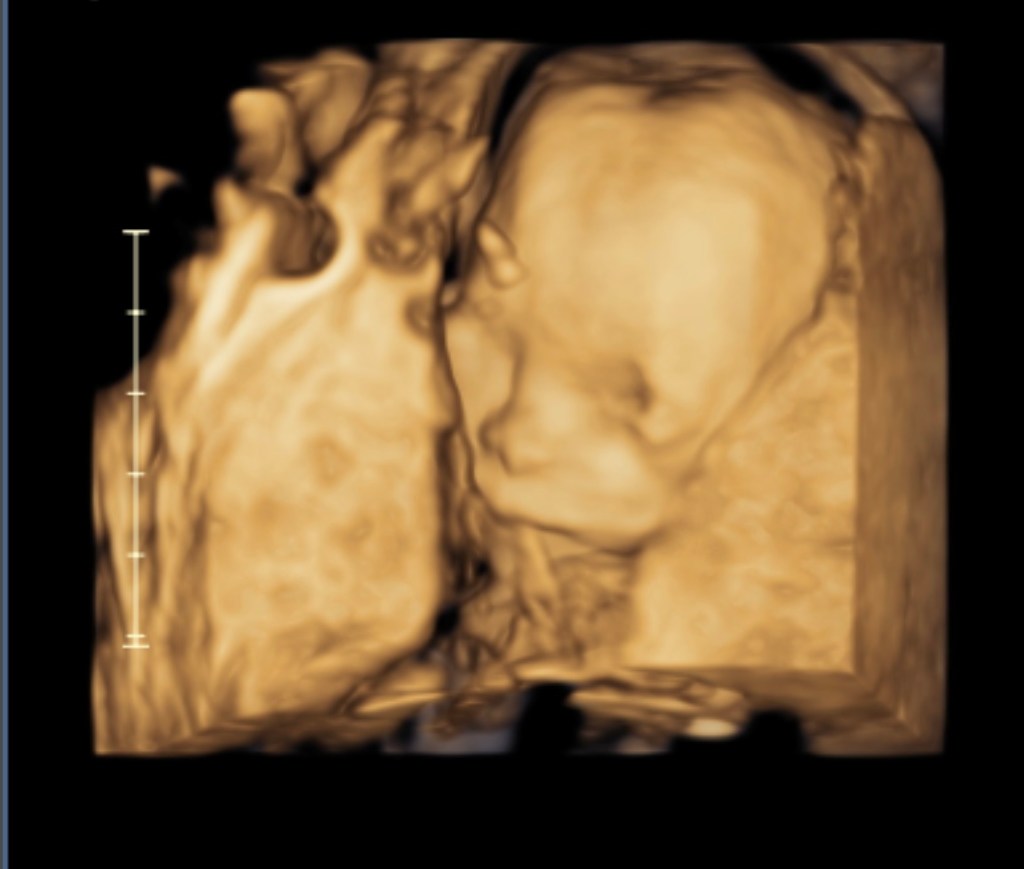

We are HALFWAY to baby which is absolutely insane. We did the big ultrasound and it went so well, we loved it and his cute face was so fun to see.